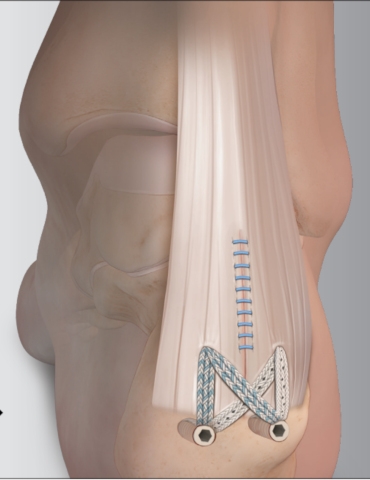

Surgery

If conservative management has failed surgical intervention may be indicated. There are various techniques that can be used. One such procedure frees the Achilles tendon from its insertion on the calcaneus after which the abnormal bone is removed. The Achilles tendon is then reattached to its anatomical insertion on the calcaneus using a suture construct with suture anchors.